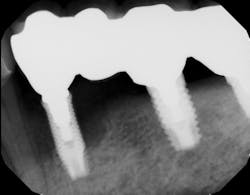

Another scenario that took place in a private practice with actual dollar amounts can be seen in treatment plan C. This patient had already paid for treatment plan B in the $5,000–$7,000 range and subsequently presented to the practice with moderate peri-implantitis. In addition to the money the patient had already invested, she would now be responsible for the financial costs of treatment plan C.

After reviewing the additional costs and lengthy healing time involved with surgery to correct the ailing implant, the overall costs associated with treatment were in the $8,000–$10,000 range, with more than three years of treatment time invested. Of important note is that most insurance companies limit the amount of reimbursement for implant-related services. When dealing with insurance companies, accurate ADA coding and claims submission are critical to facilitate services and expedite reimbursement.

In conclusion, there are many factors to consider when deciding between saving the natural dentition and extracting and placing implants. All parties must consider the long-term economic impact on the patient as well as the long-term success rates of the treatment. Both implants and periodontal therapy to save natural teeth have high initial success rates, with implants usually incurring initial costs. However, when looking at long-term retention rates, natural teeth often demonstrate fewer complications and have a smaller financial impact when correction is needed.17